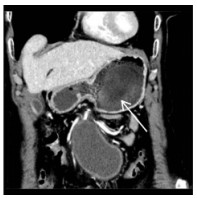

1 病例资料患者女,78岁,无明显诱因出现上腹部剧烈疼痛2 d入院,呈持续性,伴有恶心呕吐胃内容物数次、大汗淋漓、面色苍白、烦躁,否认既往高血压病史。查体:腹部叩诊呈鼓音,腹肌稍紧,全腹可及压痛,反跳痛(+/-),移动性浊音(+/-),肠鸣音弱。急诊查腹部CT示中腹部腹膜后血肿(图 1),考虑肠系膜动脉破裂可能,血肿大小约8.0 cm×4.6 cm,血红蛋白84 g/L,血压146/81 mmHg(1 mmHg=0.133 kPa)。外科专家会诊认为开腹治疗难度大,风险高,且患者及家属心理压力大,拒绝开腹手术。腹痛自行稍好转即出院。1周后患者活动时再次出现突发疼痛,症状与1周前相同。返回急诊科,经高风险谈话后接受了微创血管腔内治疗。

| 图 1 CTA发现腹腔巨大血肿,伴有瘤腔内对比剂强化(箭头示) |